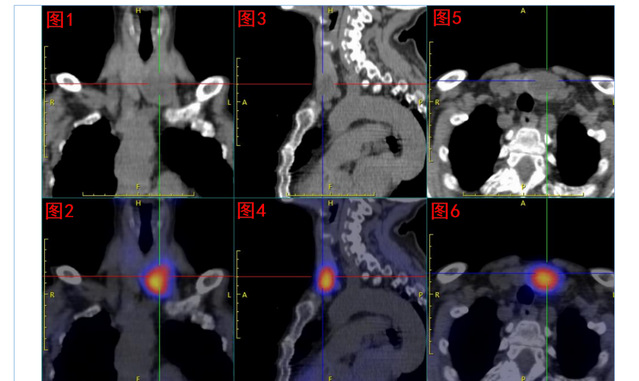

核医学科双时相甲状旁腺核素SPECT/CT显像发现:甲状腺左叶下极处显像剂异常浓聚,考虑为功能亢进甲状旁腺组织;但是该组织主体位于甲状腺左叶内,非甲状旁腺常见部位,遂反馈给吕荣主任医师团队,建议进一步行甲状旁腺及甲状腺超声检查。

99mTc-MIBI甲状旁腺SPECT/CT融合显像图:图1+2冠状位、图3+4矢状位、图5+6横断位,提示功能亢进甲状旁腺组织(十字线交叉处)。随后的超声提示:双侧甲状旁腺区多断面超声扫查未见明显异常占位性病变;双侧甲状腺结节,其中左侧叶内一枚33mm×19mm低回声、边缘光滑、内无强回声结节。颈部B超图:AB(纵切面)分别显示甲状腺左叶、甲状腺叶;左叶内一低回声结节。